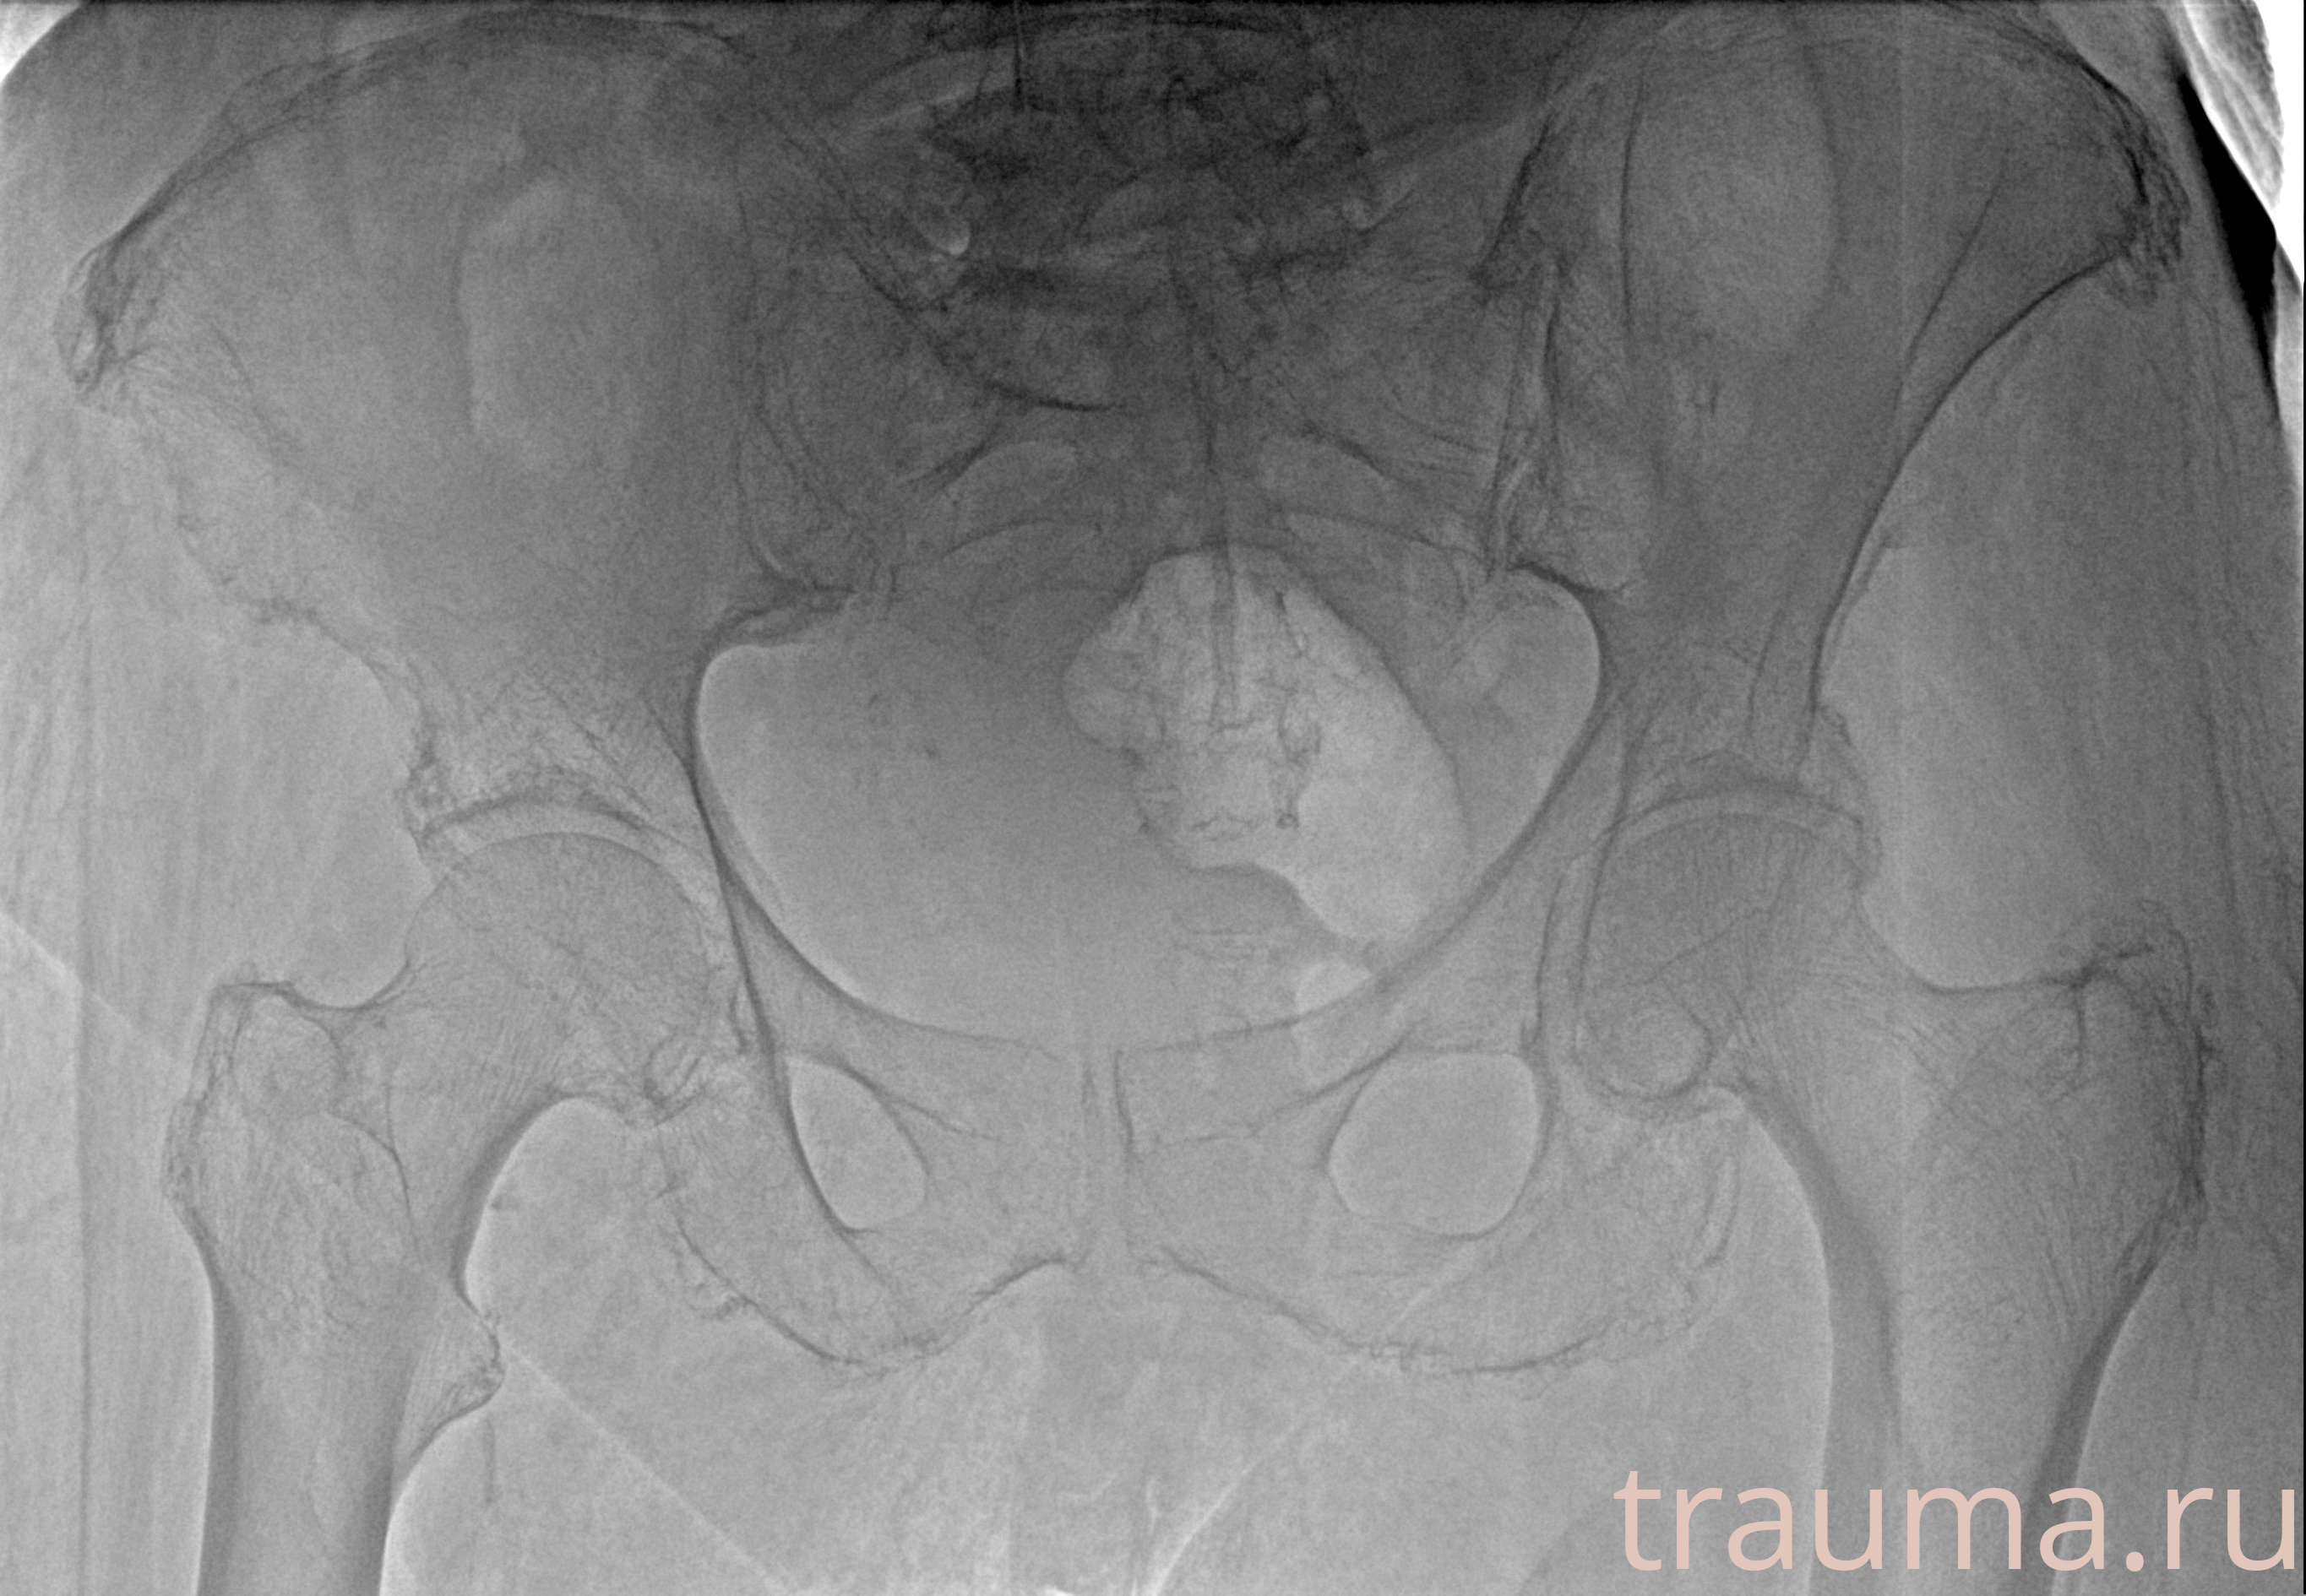

Рентген на дому: по вашему адресу приезжает врач-рентгенолог, травматолог-ортопед с мобильным рентгеновским аппаратом, проводит диагностику травмы или заболевания, делает необходимые рентгенограммы, дает рекомендации по дальнейшему лечению. Получить качественные снимки в домашних условиях возможно благодаря уникальной методике, разработанной МосРентген Центром для института  Склифосовского